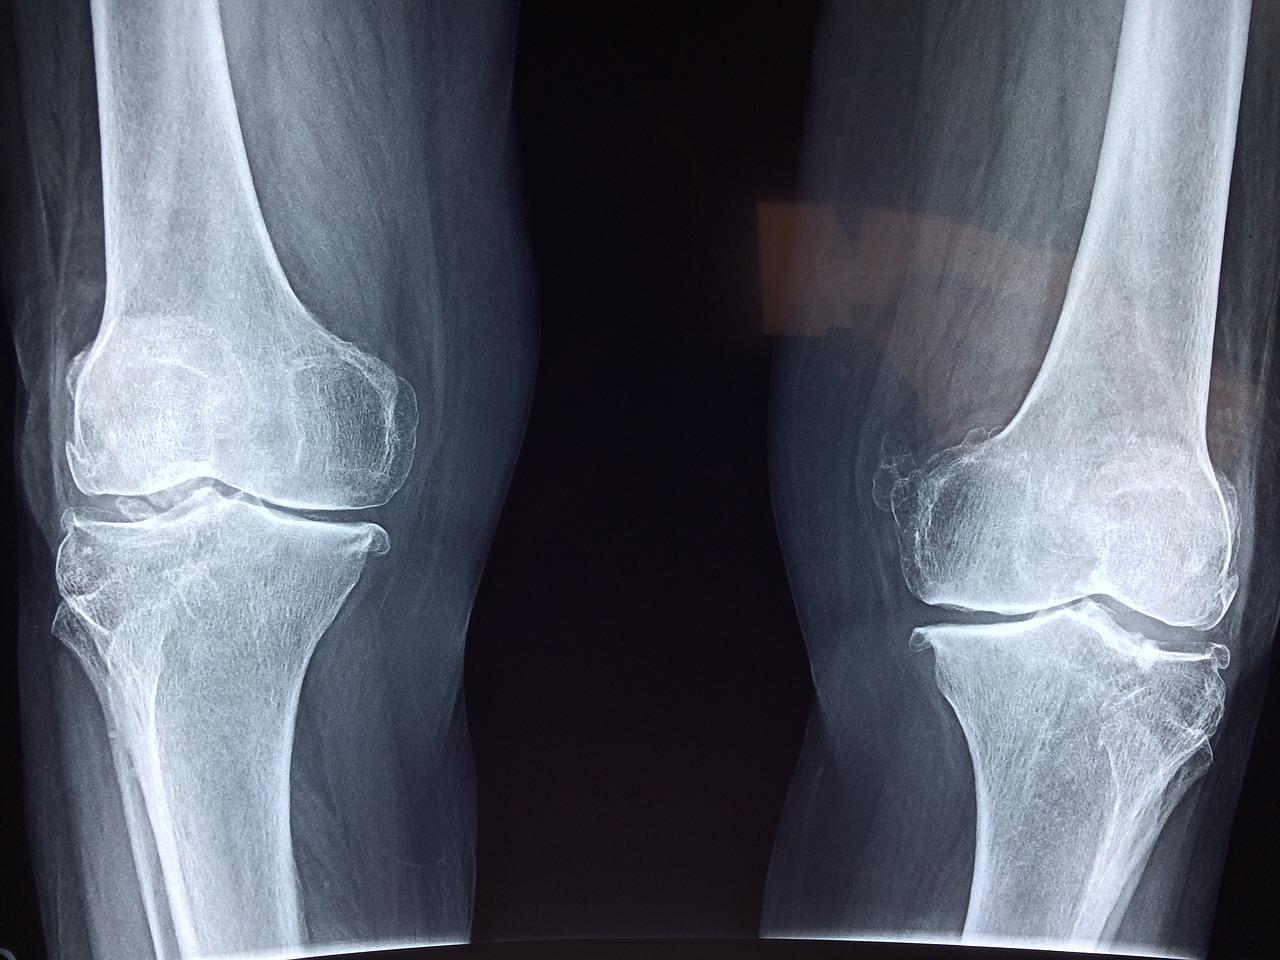

골관절염(Osteoarthritis)

골관절염은 말 그대로 관절에 발생하는 염증으로 통증과 부기가 동반된다. 주로 무릎, 엉덩이 관절, 손가락 사이 관절 등에서 호발한다. 활동을 할 수록 통증이 심해지고 노화에 따라 진행이 되는 경향을 보인다. 골관절염은 퇴행성 관절염으로도 불린다. 골관절염 환자의 경우 연골 아래 뼈가 두꺼워져 관절 사이가 좁아지며 점차 연골이 소실된다.

류마티스 관절염(Rheumatoid arthritis, RA)

류마티스 관절염은 전신성 만성 염증 질환으로 손가락뼈, 팔꿈치, 무릎, 발목 등에서 나타난다. 이는 퇴행성 관절염과 달리 30-40대에서도 발병할 수 있으며 나이에 따라 증가하는 양상을 보인다. 흔히 사지 관절에 동시에 나타나며 증상이 대칭적으로 나타나는 것이 특징이다. 또한 전신질환으로 관절, 인대 외에 다른 조직에도 류마티스 결절이 나타나는 것이 특징이다.

류마티스 관절염에서는 부종과 형질세포, 대식세포등이 축적 되며 염증성 활막이 판누스(pannus)를 형성하여 관절 연골을 덮고 뼈를 침범하여 뼈의 변형을 유발한다.